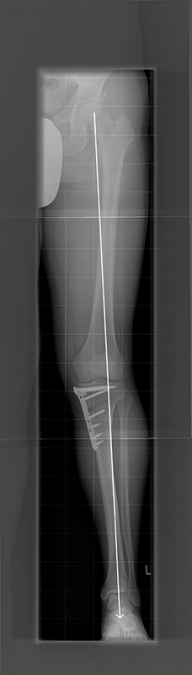

UMSTELLUNGSOSTEOTOMIE

Eine Möglichkeit der Behandlung von Verschleißleiden ist die Umstellungsosteotomie. Nach Unfällen aber auch angeboren können erhebliche Achsenabweichungen an den Beinen vorliegen. Solche Abweichungen von der zentralen Tragachse führen zu schmerzhaften Fehlbelastungen und einem vorzeitigen Verschleiß des überlasteten Gelenkabschnittes. Die Korrektur solcher Achsenabweichungen führt zu einer gleichmäßigeren Belastung des Kniegelenkes und dann auch zum Rückgang der Beschwerden.  Man unterscheidet verschiedene Techniken der Osteotomien, wie schließende und öffnende Osteotomien, die je nach Fehlstellung und vorliegendem Verschleißbild angewendet werden können.

Wir führen Umstellungsosteotomien nach Analyse computerunterstützt durch. Hierdurch kann eine hohe Genauigkeit bei der Durchführung erzielt werden.

Nach solchen Operationen ist in den meisten Fällen eine Teilbelastung notwendig, um die Knochenheilung zu schützen. Der Prozess der „Umgewöhnung“ des Gelenkes nimmt eine Zeit von ca. 3 -6 Monaten in Anspruch. Es kann durch solche Korrekturen in vielen Fällen ein künstliches Gelenk über 10 Jahre und mehr vermieden werden.

Bild HTO mit Tomofixplatte nach OP